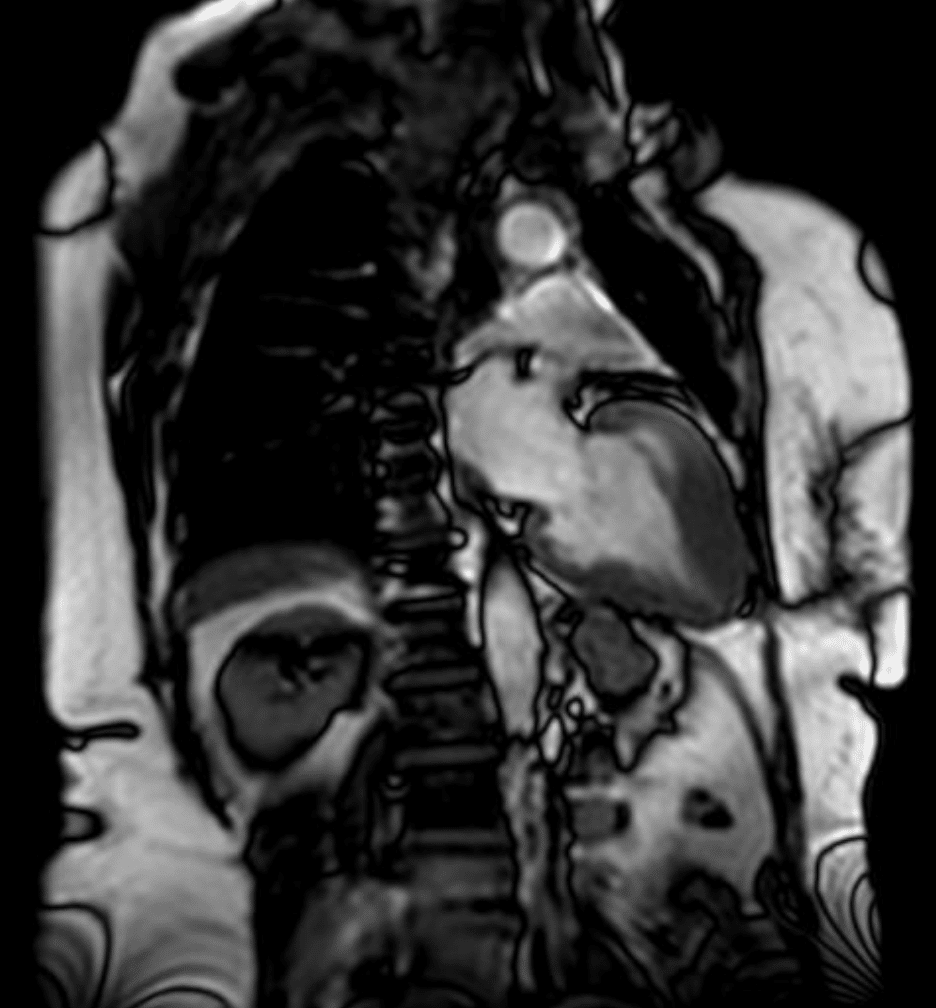

Cardiac MRI

A cardiac MRI with findings suggestive of apical hypertrophic cardiomyopathy. The left ventricle is observed in the right view at the end of diastole with “ace of spades” shape, characteristic of Yamaguchi syndrome